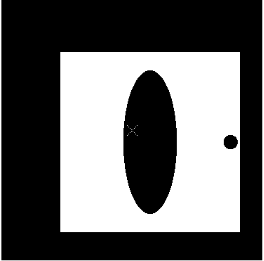

本题第一小问X射线间隔问题:利用matlab进行分类将X射线分有衰减射线和无衰减射线,无衰减射线接受数据为0,有衰减射线接受数据不为0,以是否为0作为依据对接受信息附件sheet2进行查找,具体matlab程序见附录程序一,当X射线与椭圆长轴垂直时射线分类情况及每类的条数如图一所示

图 1

当X射线与椭圆长轴平行时射线分类情况及每类的条数如图二所示

图 2

由分类数据可轻易看出有一个值大体是恒定不变的因为该数据表示X射线通过圆的衰减射线条数如表一所示

由于再次我们取平均值条X射线有衰减现象可得d为0.2909毫米如下:

5.1.2模型建立与求解

本论文通过求正方形的四条边从而确定正方形的中心。如图1所示最下侧的X射线为CT的射线的最下边缘,最上侧的X射线为为CT的射线的最上侧边缘。如图2所示最左侧的X射线为CT的射线的最左边缘,最右侧的X射线为为CT的射线的最右侧边缘。有上图的4个边缘组成一个正方形,该正方形中心为CT扫描的旋转中心O1,并且可求O在模版中的以模版坐下角为原点O2的坐标,本论文采用填补法,将X射线4个边缘组成的正方形填补到原来模版周围,用如下公式求模版各个边需要填补的像素:

接着求出大正方形的中心的像素坐标,大正方形的像素矩阵r为370*372,由于误差不到1mm,所以本题忽略不记,旋转中心为正方形像素中性r(185,186),将像素中心转化为以模版左下角O2为原点的坐标(m,n),转换公式如下:

O1为旋转中心其在模版上的位置如上图白色标记,坐标为: